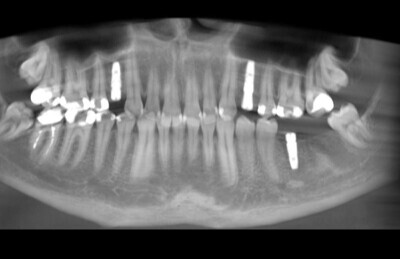

Navigovaná chirurgia, 3 implantátov

Autor práce Dr. Michal Repaši

Zubný technik Vasil Csopej